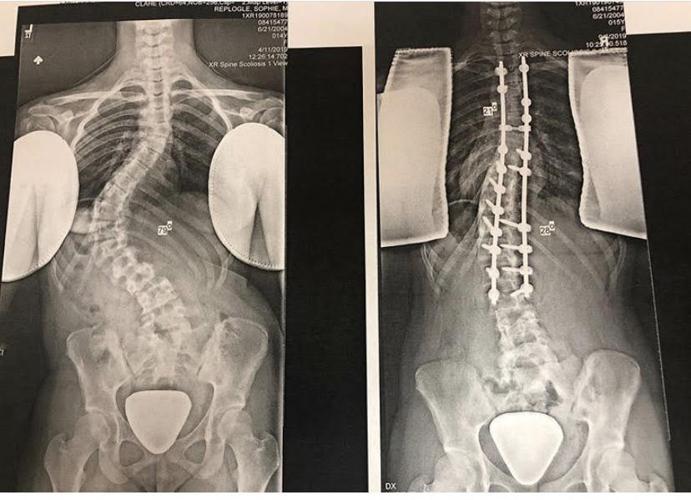

Scoliosis surgery helps Pioneers' volleyball player Becca Cohen get Can U Play Volleyball With Scoliosis This information is intended for teenagers with scoliosis who are undergoing. Can you play sports with scoliosis? Sports like volleyball or baseball can be played with scoliosis, particularly when they are modified to suit your capabilities. Otherwise, you can rest at ease—your child will likely be able to pursue athletic activities while being treated for scoliosis with back bracing. Scoliosis. Can U Play Volleyball With Scoliosis.